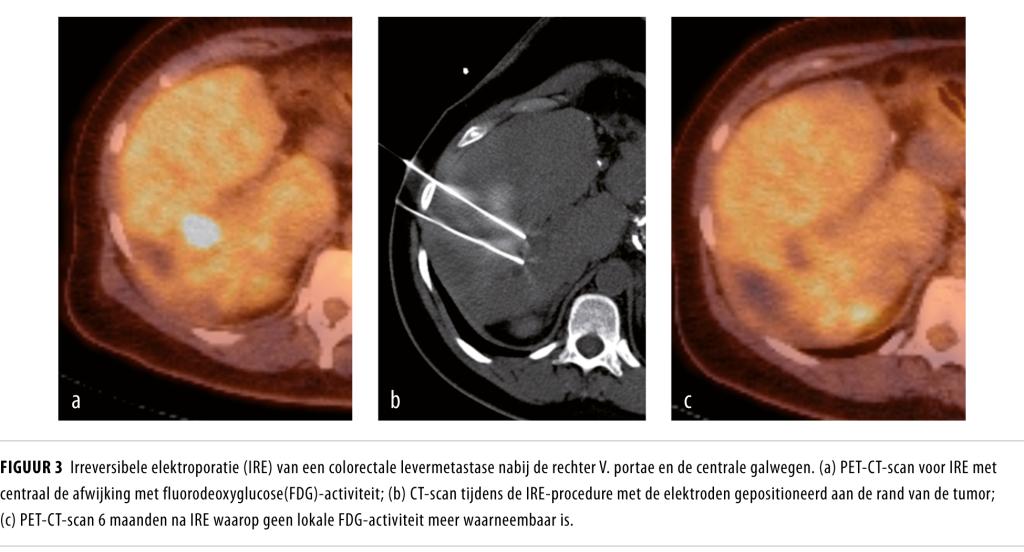

Figuur 3

Er zijn verschillende studies gepubliceerd naar de effectiviteit van IRE voor centrale levertumoren (tabel 2).3-7 Volledige remissie na een follow-up variërend van 3-18 maanden was 55-93% (93-100% voor tumoren 8 Na percutane IRE bij LAPC werd eveneens goede lokale tumorcontrole gezien (n = 14) (figuur 3).9Langetermijnresultaten zijn echter nog onbekend.